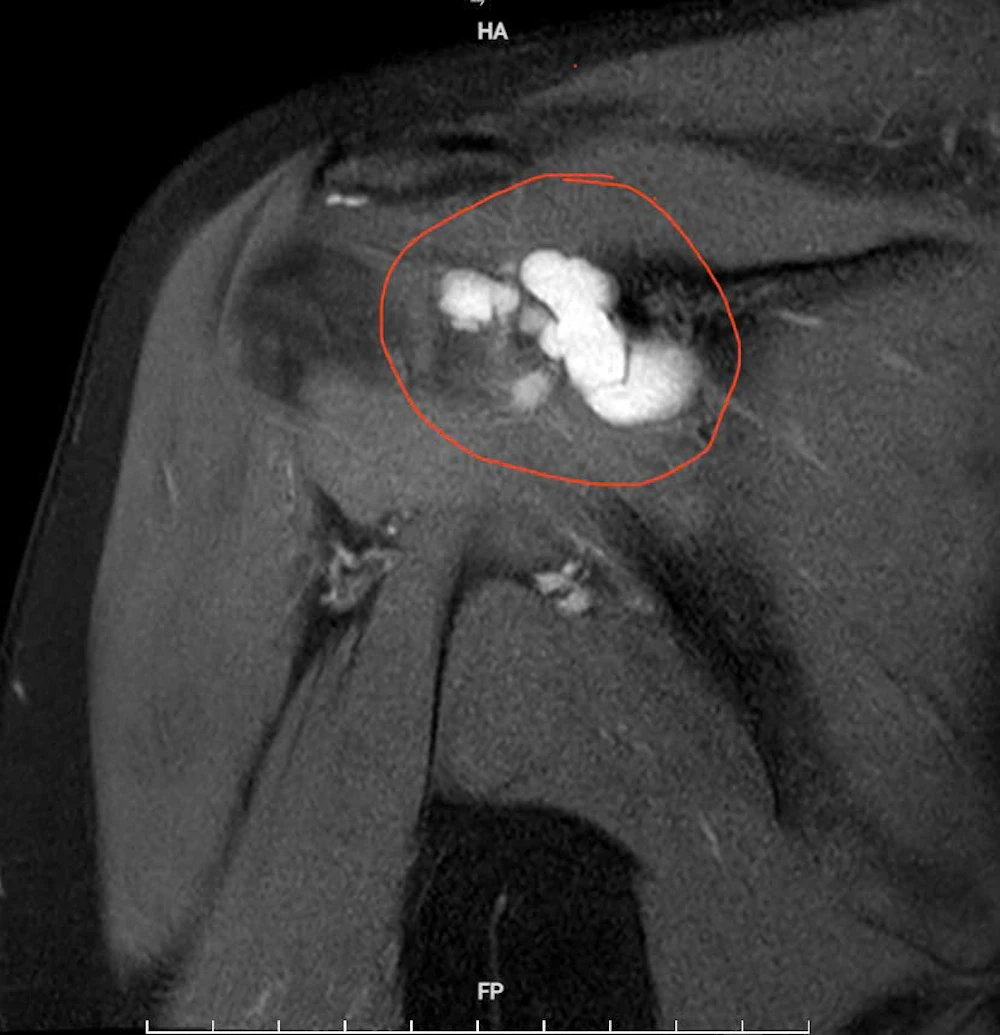

Qua thăm khám lâm sàng kết hợp chẩn đoán hình ảnh, các bác sĩ xác định bệnh nhân mắc u bao hoạt dịch khớp vai phải - một bệnh lý ít gặp trong thực hành lâm sàng. Kết quả chụp cộng hưởng từ (MRI) cho thấy khối u kích thước khoảng 4×2 cm, gây hẹp khoang mỏm cùng vai và chèn ép các cấu trúc xung quanh.

Hình ảnh chụp cộng hưởng từ (MRI) khối u kích thước khoảng 4×2 cm gây hẹp khoang mỏm cùng vai, chèn ép các cấu trúc xung quanh.